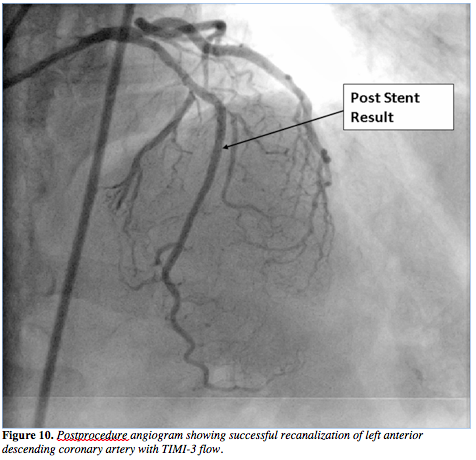

was then advanced through the subintimal dissection into the proximal LAD (Figure 6) and then the Corsair was advanced over this wire proximal to the CTO segment. As a result, the true lumen of the distal LAD was then successfully negotiated with a Fielder XT guidewire in an antegrade fashion (Figure 7). The retrograde wire with Corsair was removed. After successful balloon dilatation, two Yukon stents (Translumina) of 2.5 x 32 mm and 2.5 x 28 mm were deployed (Figures 8 and 9), with an optimal angiographic result (Figure 10 and Video 2). The patient is free of symptoms after 6 months of follow-up.